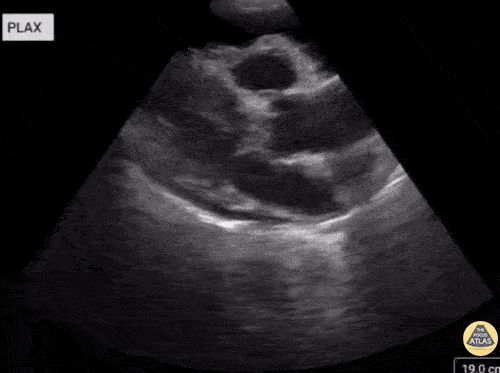

This is a 58-year-old female with history of metastatic lung cancer who presented with escalating dyspnea. POCUS revealed an anechoic region remaining anterior to the descending aorta with parasternal long axis view highlighting diastolic right ventricular collapse, and subxiphoid view highlighting systolic right atrial collapse. She subsequently went for pericardial window. Krishna Patel, DO Lauren Lowes, DO Julia Tu, MS4 Central Michigan University College of Medicine